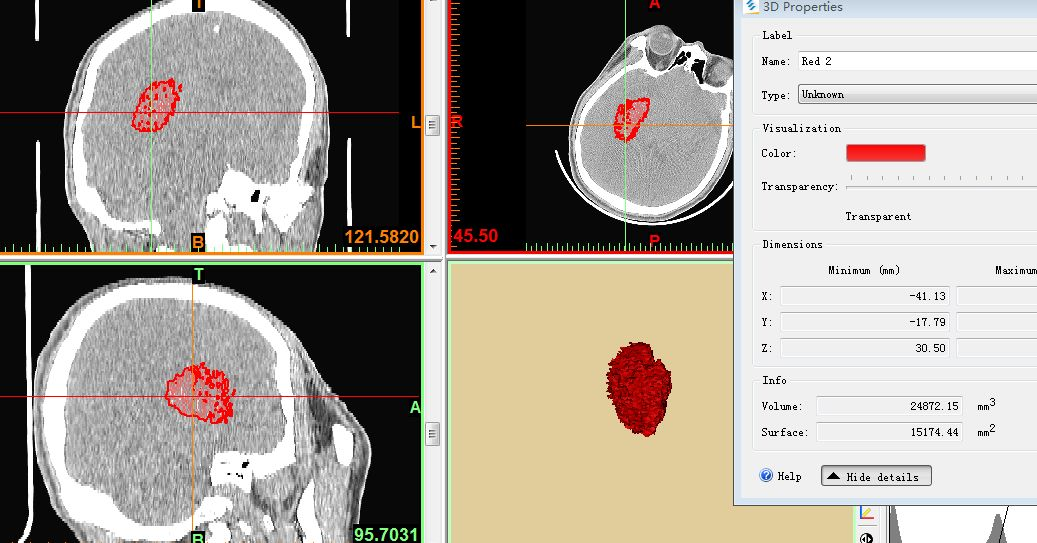

应用3D重建,CT域值设定在55-100,重建血肿量为16.7ml。

把CT阈值设定为44--100重建血肿量为24.87ml(此血肿量包括分层的高密度血肿及低密度血肿)。

剖开24.87ml血肿看看血肿的分层情况,绿色的为CT阈值设定为55--100时高密度的血肿,红色的为CT阈值设定为44--100时增加的分层低密度血肿。

因为病人意识呈进行性加重、头痛较入院时明显,虽然血肿量为24.87ml,但三脑室受压明显,血肿周围的低密度(上图红色的部分)通过两次CT对比考虑为血肿周围析出的血清部分或长期饮酒造成的特殊血肿形态--分层结构,排除活动性出血;因其长期饮酒,担心其开颅术中止血困难,与家属在3D下沟通后拟行微创穿刺置管引流术。